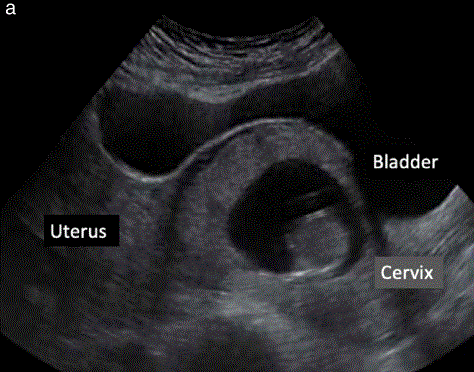

胎盘/妊娠囊的低前部植入,靠近或位于瘢痕憩室中,是与PAS疾病相关的最常见的早期超声征象(图3a)。根据当地资源的不同,可以在有剖宫产史的妇女在妊娠早期扫描时使用经阴道超声进行检查。在暴露疤痕上植入PAS的风险,具有极好的阴性预测价值。

在早孕期,可能早产的妇女往往比足月分娩的妇女子宫颈更短;妊娠早期和中期宫颈长度测量相关。在妊娠的早期测量子宫颈(图3b),可能结合个人病史,可以确定一组早产风险增加的人。

图3 (a)剖宫产疤痕妊娠超声图像,位于宫颈顶部,膨入膀胱。确定胎盘位置与既往剖宫产瘢痕可能有助于早期发现异常侵入性胎盘。(b)超声图像显示了妊娠11 + 0至14+00周时宫颈长度(A至B)和峡部(B至C)的测量。